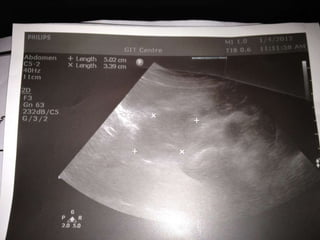

A 43-year-old Arabic woman presented with dyspepsia, vomiting, and weight loss for one month. On examination, she had evident weight loss but no other abnormalities. She was diagnosed with pancreatic head cancer and sent to surgery for bypass surgery and a histological diagnosis. This case demonstrates that dyspepsia with alarm features like weight loss and anemia in those over 45 should prompt consideration of pancreatobiliary causes and appropriate imaging if upper GI pathology is not found.